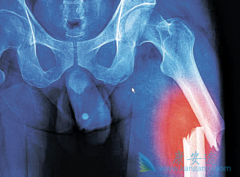

骨髓瘤能活多久 ?有个案例是70岁的李老太由于反复出现骨折只能入院治疗。谁知在治疗时,又被查出患有多发性骨髓瘤,这结果让李老太和她的家人都感到震惊。其实这样的事情很常见。中老年人常出现的问题骨头痛、骨折、多尿……不一定就是缺钙或者是身体 ...

• 如何识破那些引起骨髓瘤症状的错误诊治

骨髓瘤患者的临床表现往往是身体多器官,多部位的,同时,由于人们对这个病认识不充足,导致对某些常见 骨髓瘤症状 表现,比如腰酸背痛,关节疼痛,感染现象等,常常出现误诊误治的现象,最终可能会延误治疗时机,影响预后。   如何识破那些引起骨髓瘤 ...

• 什么是多发骨髓瘤?如何看多发骨髓瘤的严重程度

多发骨髓瘤 单看疾病的命名,大多数患者会自然的认为是“实体瘤”。其实并不是这样,这个主要是指骨髓内的造血细胞异常,这种细胞叫做浆细胞,是白细胞的一种。也就是产生人体抗体免疫球蛋白的细胞。要看多发骨髓瘤严重程度,比较直接是看原始浆细胞比 ...